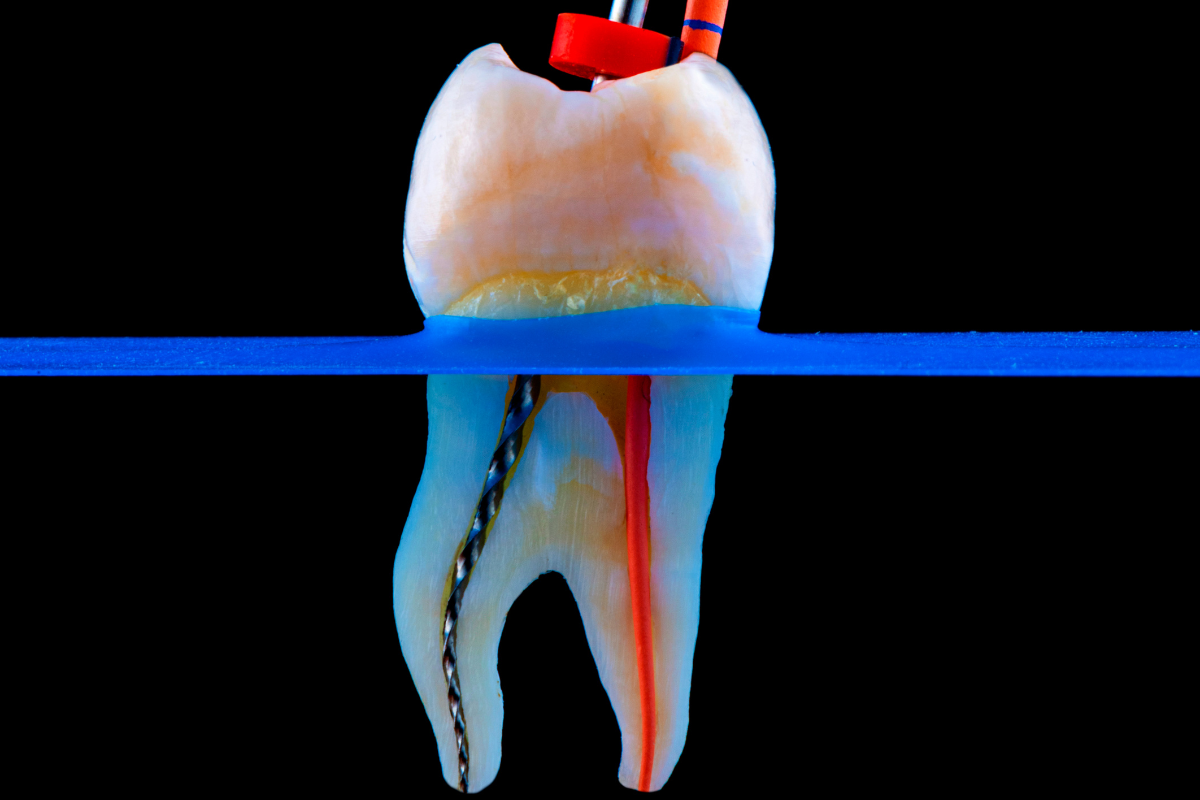

Uvnitř každého zubu se nachází tzv. zubní dřeň (pulpa) – měkká tkáň složená z nervů a cév. Pokud se bakterie dostanou až k dřeni kvůli hlubokému kazu, prasklině nebo úrazu, může dojít k zánětu nebo infekci. Endodontické ošetření dřeň odstraní, kanálky vyčistí, dezinfikuje a zaplní speciálním materiálem.